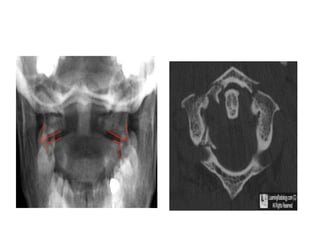

Odontoid View

• An adequate film should include

the entire odontoid and the lateral

borders of C1-C2.

• Occipital condyles should line up

with the lateral masses and

superior articular facet of C1.

• The distance from the dens to the

lateral masses of C1 should be

equal bilaterally.

• The tips of lateral mass of C1

should line up with the lateral

margins of the superior articular

facet of C2.

• The odontoid should have

uninterrupted cortical margins

blending with the body of C2.

• C1 ring fracture:

• Sudden severe load on the top of the head may cause

a ‘bursting’ force which fractures the ring of the atlas

(Jefferson’s fracture).

There is no encroachment on the neural canal and,

usually, no neurological damage.

• The fracture is seen on the open-mouth view (if the

lateral masses are spread away from the odontoid peg)

and the lateral view.

• A CT scan is particularly helpful in defining the fracture.

• If it is undisplaced, the injury is stable and the

patient wears a semi-rigid collar or halo-vest until

the fracture unites.

• If there is sideways spreading of the lateral

masses (more than 7 mm on the open-mouth

view), the transverse ligament has ruptured;

• this injury is unstable and should be treated by a

halo-vest for several weeks.

• If there is persisting instability on x-ray, a

posterior C1/2 fixation and fusion is needed.

• A hyperextension injury can fracture either